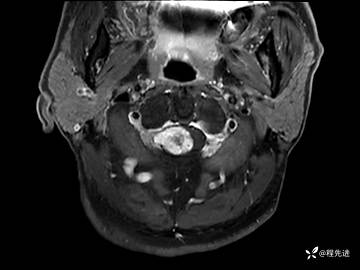

MRI平扫+增强:

T1增强: